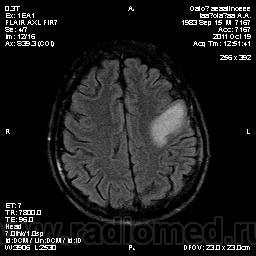

Колеги, спасибо за высказывания. В данном случае про наркоманский анамнез указано не спроста... Есть мнение, что в этом лежит точка отсчета.... По поводу абсцесса и гематомы - не согласен; по поводу первого - нет соответствющей клиники, по поводу второго - не характерна локализация и сигнальные характеристики. Не буду томить общественность касательно собственного мнения. Есть две гипотезы, о которых думается в данном случае: прогрессирующая лейкоэнцефалопатия и новообразование... Но без контраста их не разрешить...

пожалуй "первое", но в отношении "второго"смущает "круглит" на вершине "воспалительной демиелинизации", который она (демиелинизация) так странно обходит...

Имеются  в виду последние 2 картинки?Мне тоже так показалось.А почему контрастирования не будет?Чем контрастируете?